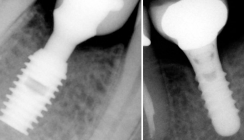

Dem Patienten wurden verschiedene ­Therapieoptionen aufgezeigt und auf die jeweiligen Vor- und Nachteile eingegangen. Nach intensiver Beratung entschlossen wir uns auch im Hinblick auf die Erweiterbarkeit und unter Berücksichtigung monetärer Erwägung für eine Teleskopversorgung auf NEM-Basis. Als natürlicher Pfeilerzahn wurde Zahn 15, 14, 12, 11 im Oberkiefer sowie Zahn 33, 43, 44 primärüberkront. Um eine lineare Abstützung und die damit einherge­henden, prognostisch ungünstigen Kippbewegungen zu vermeiden, sollte durch die Insertion von Implantaten Regio 23 und 24 ein ausgeglichenes Abstützungspolygon geschaffen werden. Nach der Extraktion der nicht erhaltungswürdigen Zähne und der druchgeführten Parodontaltherapie erfolgte eine Abheilphase von zehn Wochen. Es zeigte sich im Bereich des posterioren Alveolarkamms eine ausgeprägte Oberkieferatrophie mit unzureichendem vertikalen Knochenangebot beidseits. Um eine Sinusbodenelevation mit anschließender Augmentation zu vermeiden, wurde im Rahmen der Planung mittels 3-D-Diagnostik (digitale Volumentomografie) die Insertion von Kurzimplantaten in Erwägung gezogen. Die metrisch-präoperative Analyse mittels digitaler Volumentomografie (GALILEOS Comfort, Sirona Dental) ergab ein vertikales ­Knochenangebot von 9,7 mm Regio 23 und 6,2 mm Regio 24. Die transversale Messung der krestalen Kieferkammbreite betrug 6,6 mm Regio 23, respektive 6,4 mm Regio 24. Bedingt durch das eingeschränkte Knochenangebot wurde auf längenreduzierte Implantate (4,5 x 8 mm, Bicon Dental Implants) zurückgegriffen. Die Verwendung von Implantaten zur Pfeilerzahnvermehrung für die Aufnahme einer Hybridprothese ist in der modernen Zahnheilkunde ein routinemäßiges Verfahren. Der Einsatz von Primärkronen auf Kurzimplantaten für eine implantologisch-prothetische Rehabilitation ist jedoch bis dato noch nicht beschrieben worden.

Nach Infiltrationsanästhesie Regio 22–24 wurde nach krestaler Schnittführung ein Mukoperiostlappen nach bukkal mobi­lisiert und der Kieferkamm freigelegt. Die Vorbereitung des Implantatlagers wurde entsprechend des Bohrprotokolls unter der Verwendung der Implantatbohrer aufsteigenden Durchmessers ohne Wasserkühlung bei 50 /min durchgeführt. In Regio 24 erfolgte ein interner Sinuslift mithilfe der im Implantatset enthaltenen Osteotome. Die Implantate wurden ca. 1–2 mm subkrestal eingeklopft und die Achse mit einem Einbringinstrumentarium justiert. Der sich durch die angeschrägte Implantatschulter („sloping shoulder“) ergebende Spalt zwischen Implantatschulter und Implantatschacht wurde mit den bei der Implantatbohrung gewonnenen autologen Knochenspänen zirkumferent ausgefüllt.13

Bei komplikationsloser Wundheilung konnten die Implantate nach drei Monaten Einheilzeit freigelegt werden. Bei adaptiertem Wundverschluss erfolgte drei Wochen später die Präparation der Pfeilerzähne sowie die geschlossene Abformung nach der Repositionstechnik. Die teleskopierende Ober- und Unter­kieferversorgung wurde definitiv mit RelyX (3M ESPE) eingesetzt.